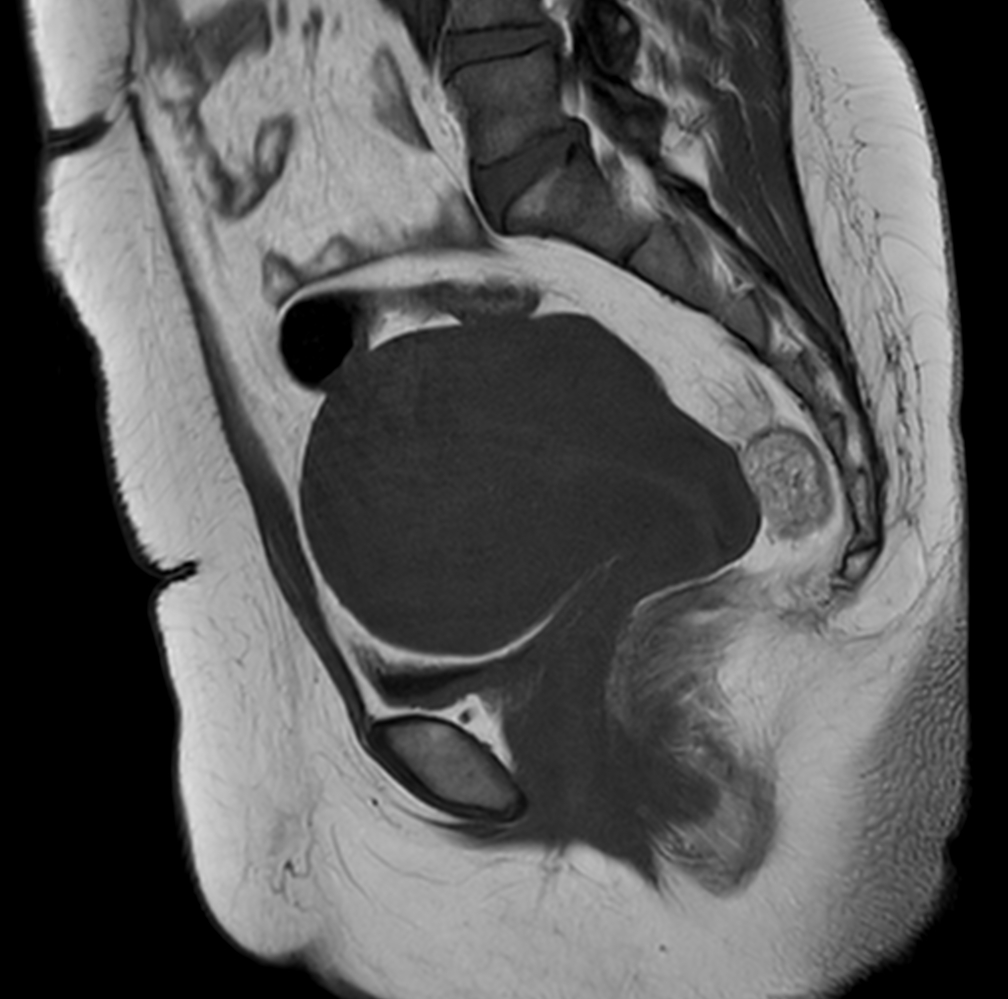

Sagittal T2w TSE